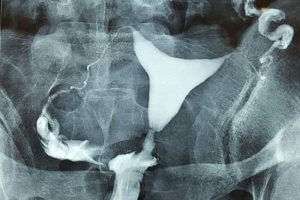

Myom

Rahim sağındaki iri myom kitlesi rahim boşluğu alt kısmının uzamasına ve sola doğru itilmesine sebep olmuş.